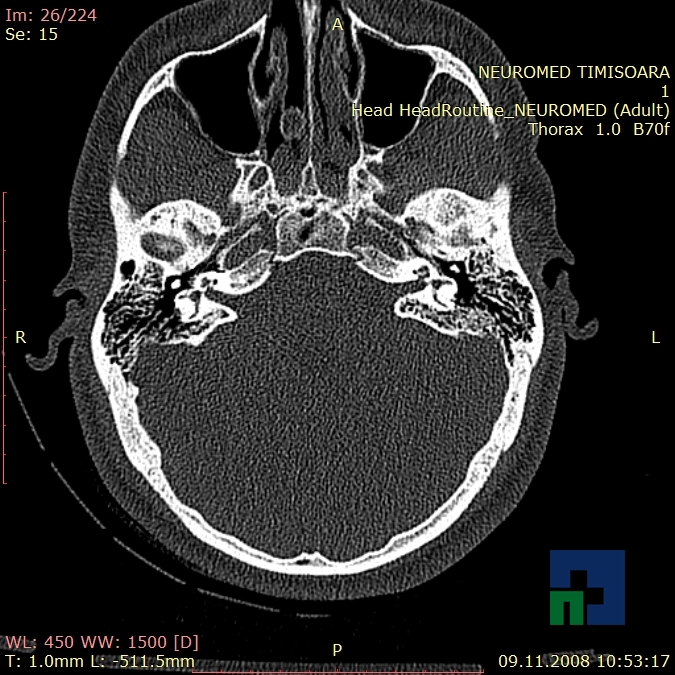

În cazul traumatismelor cranio-cerebrale:

- Evaluarea deplasării liniei mediane

- Evaluarea cisternelor perimezencefalice

- Diagnosticul edemului cerebral, a contuziei cerebrale, a leziunilor axonale difuze edematoase/hemoragice, a dilacerării cerebrale, a hematomului intraparenchimatos posttraumatic, a hematoamelor subdurale/extradurale (acute, subacute, cronice), a hemoragiei intraventriculare, a hemoragiei subarahnoidiene

- Diagnosticul traumatismelor de bază de craniu